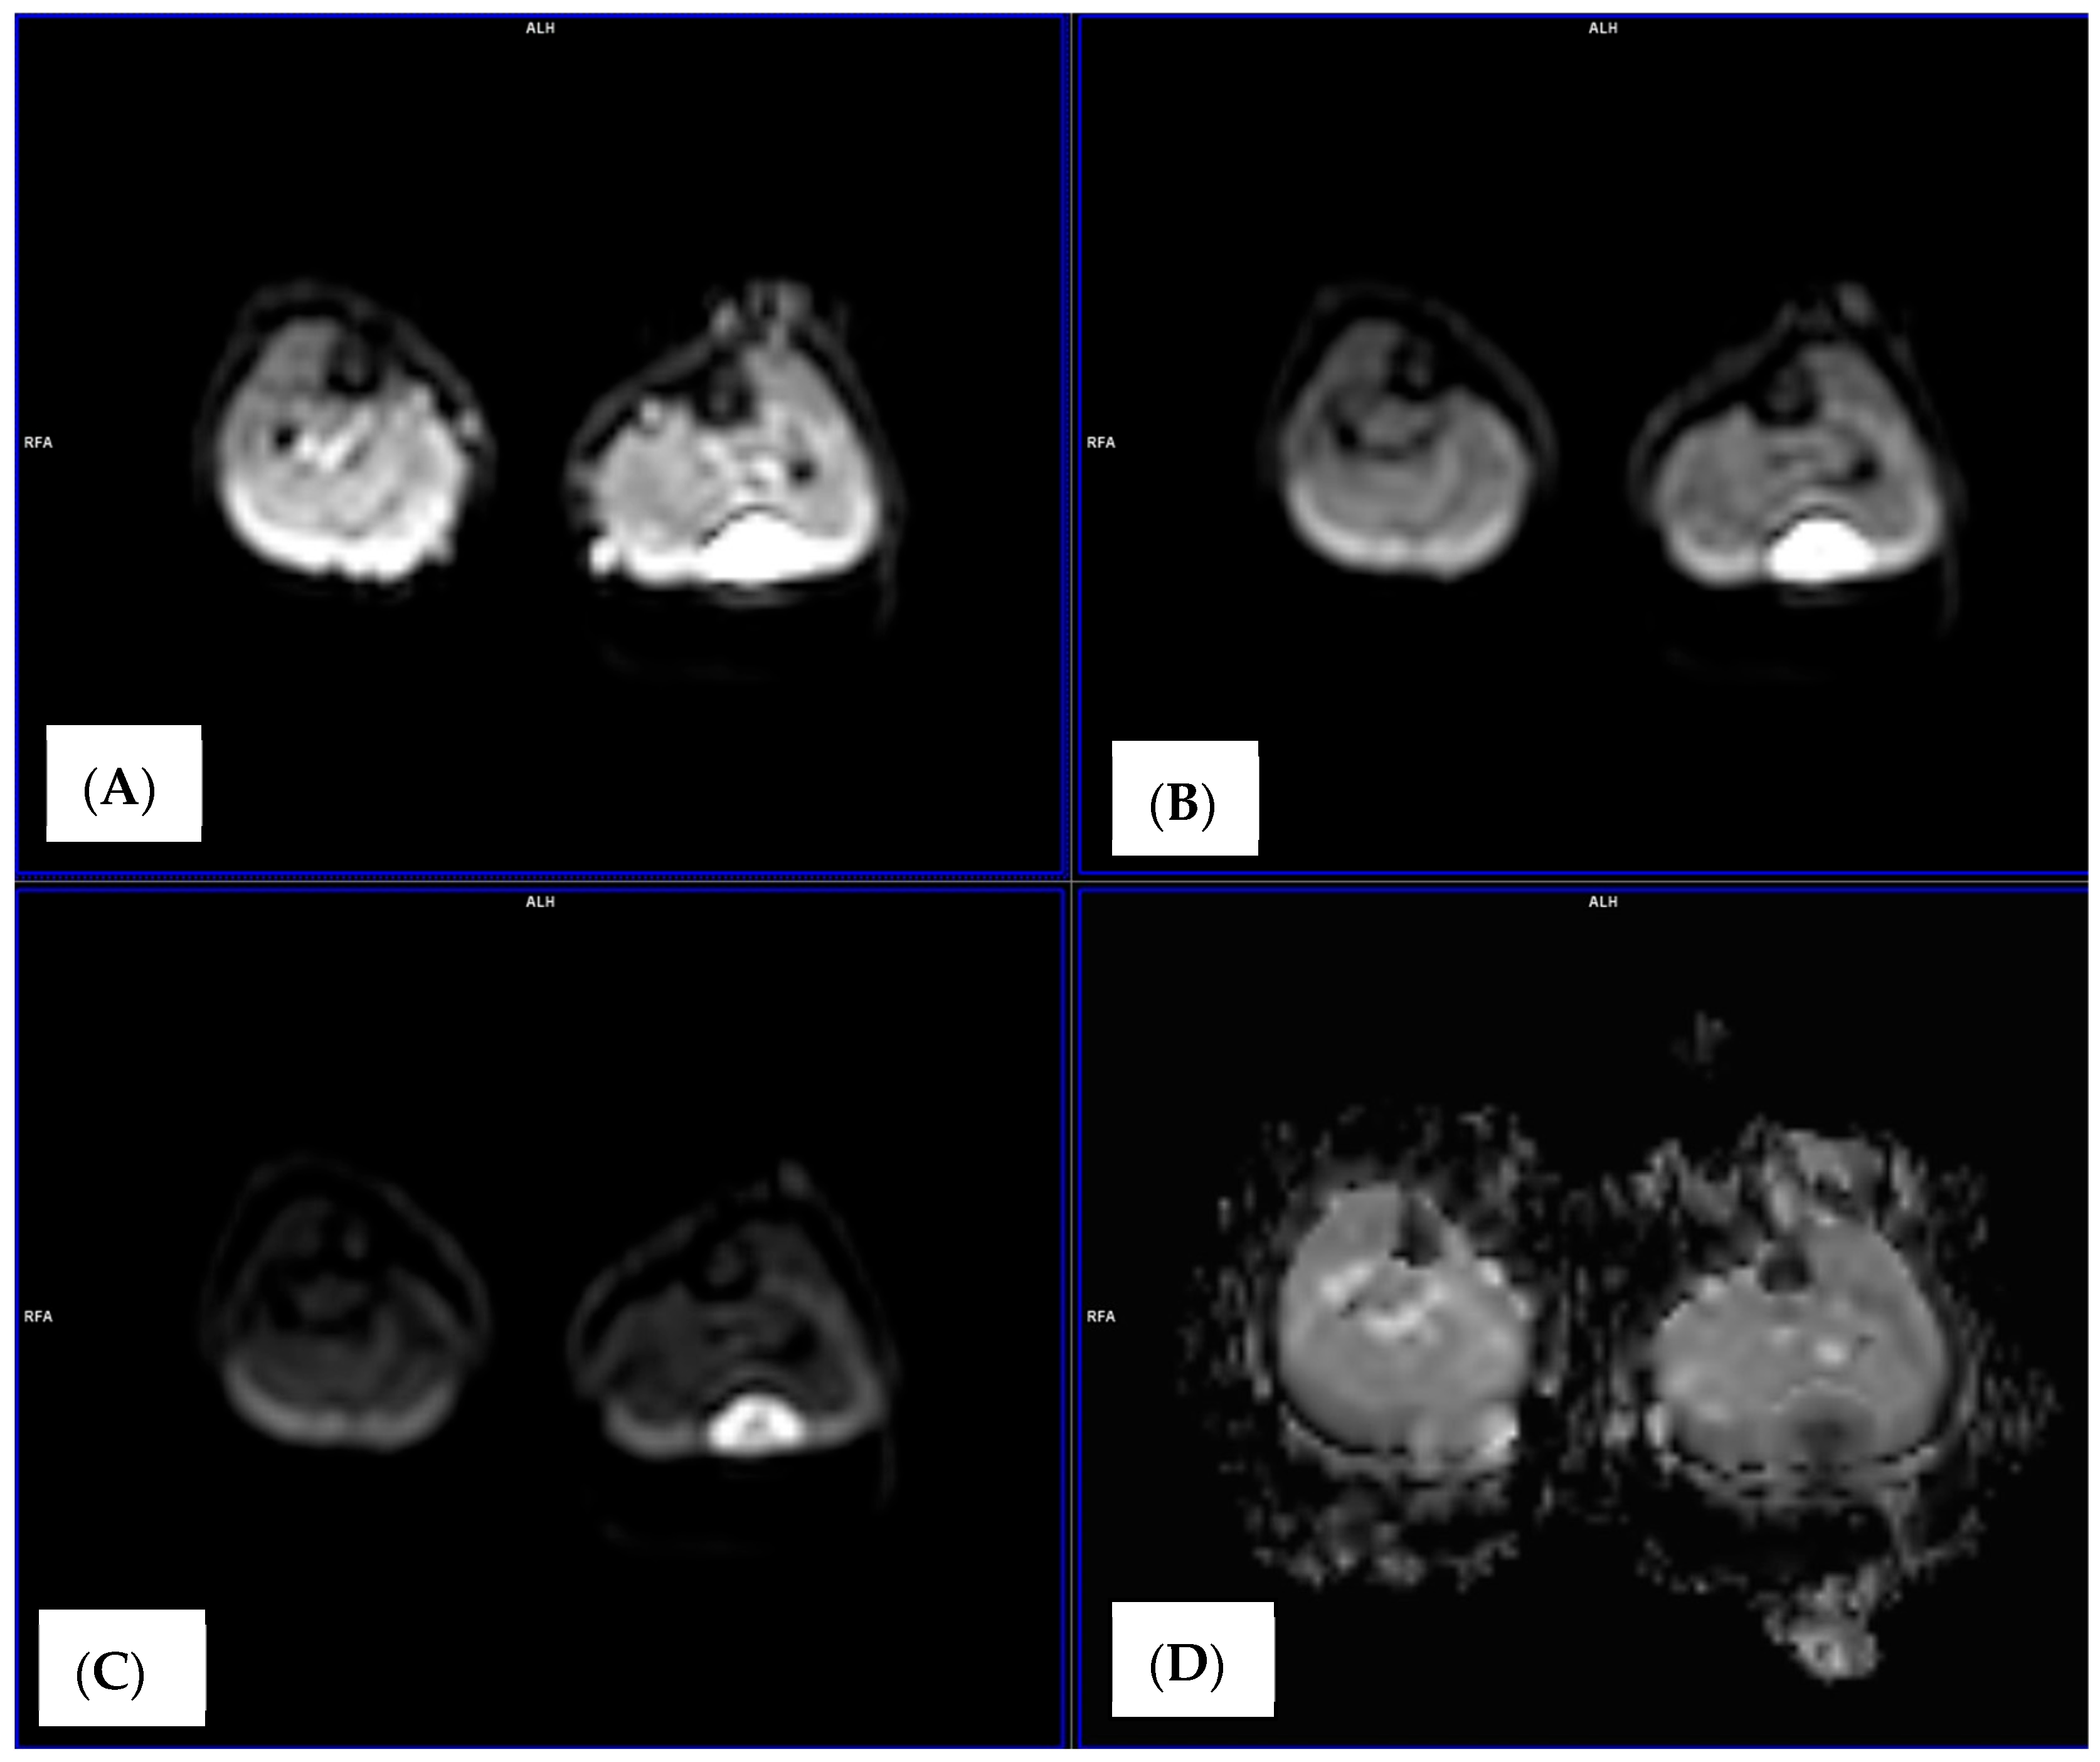

2.4. Image Analysis and ADC Measurements

3.2. ADC Changes After Chemotherapy

4. Discussion